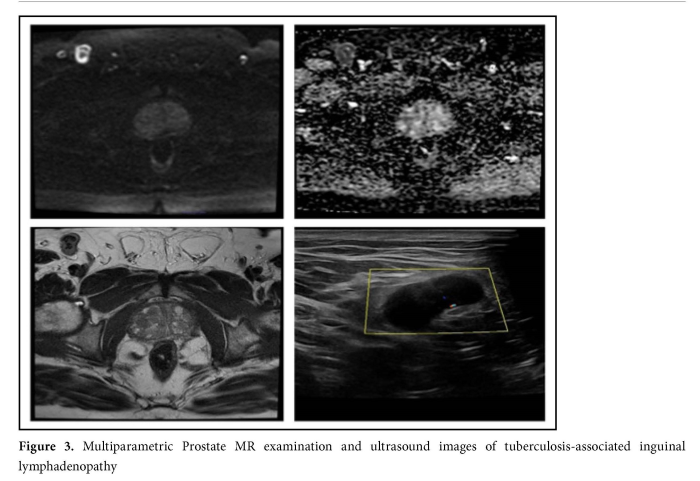

In our series, 315 IEPFs were unrelated to the genitourinary system (Table2, Figure 4). Inguinal hernia was detected in 187 cases. Of these patients, five had both bowel and fatty tissue herniation, whereas 182 had only fatty tissue herniation. Other findings included T1-T2 hypointense sclerotic bone lesions initially considered as enostosis (n=85), free fluid in the pelvis (n=13), trochanteric bursitis (n=3), metastatic lesions in the pelvic bones (n=2), trauma-related fracture in the coccygeal bone (n=2), aneurysmal bone cyst in the pubic bone (n=1), lymphocele (n=1), lumbosacral transitional vertebral anomaly (n=12), Tarlov cyst (n=5), and avascular necrosis (n=1) (Figure 2). In one case with a PI-RADS score of 2, suspicious multiple obturator and pararectal lymphadenopathies were detected. Sampling of these adenopathies led to the diagnosis of chronic lymphocytic leukemia.In another case, rectum invasion was observed. In another case with a PI-RADS score of 2, the sonographic examination performed due to a centrally vascularized inguinal lymphadenopathy without a fatty hilum and with asymmetrical cortical thickening led to the diagnosis of tuberculosis (Figure 3).